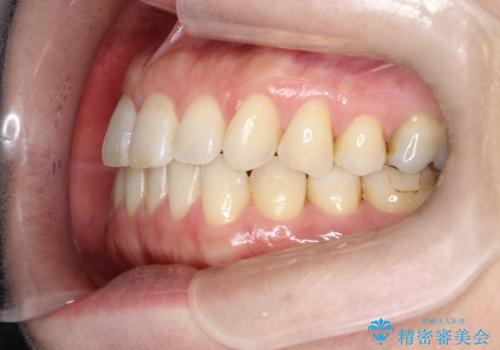

- 右上の前から2番目と3番目の歯が内側に引っ込んでしまっているのを主訴に来院されました。

右上の2番目と3番目のはが前後反対にかんでしまっている状態でした。

インビザラインにて治療することとしました。

内側に引っ込んでいる歯も、インビザラインにてしっかり外側に動かすことができます。